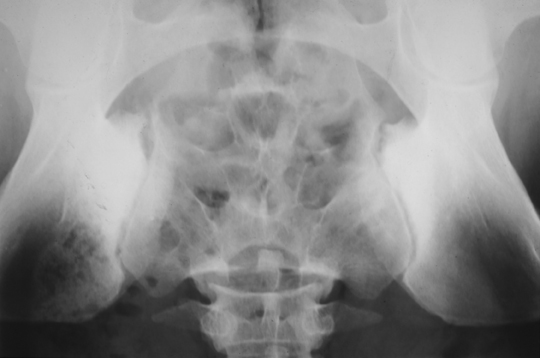

Osteitis Condensans Ilii

N. K. AKRITIDIS, MD, S. PAPADOPULOU, MD,

T. PAPAXANTHIS, MD and S. T. TSIOURIS, MD

G. Hatzicosta General Hospital, Ioannina, Greece

An 88-year-old woman with a history of senile cardiac amyloidosis was seen in the cardiology clinic for heart failure. During the visit, she reported that she had had persistent pain along the lumbo-sacral...